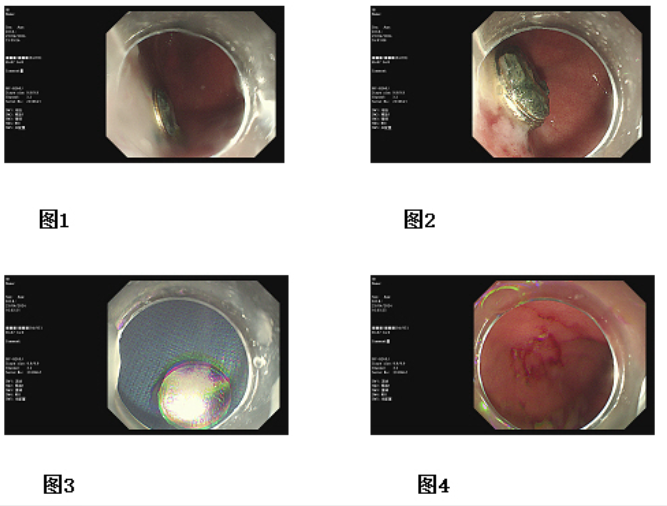

在麻醉科的通力配合下,消化內(nèi)科陳欣主任親自手術(shù)。陳主任使用一次性取石網(wǎng)籃網(wǎng)套住胃底紐扣電池,輕輕上移,這個(gè)過程不能有一點(diǎn)閃失,紐扣電池一旦落入腸腔,必須進(jìn)行開腹手術(shù)。紐扣電池胃里停留時(shí)間越長(zhǎng),堿性液泄露的可能性越大,一旦泄露,對(duì)食管、胃的腐蝕,將影響孩子的終身。5分鐘的操作,陳主任將紐扣電池成功脫出口腔,堿性液一點(diǎn)未滲漏,患兒化險(xiǎn)為夷。